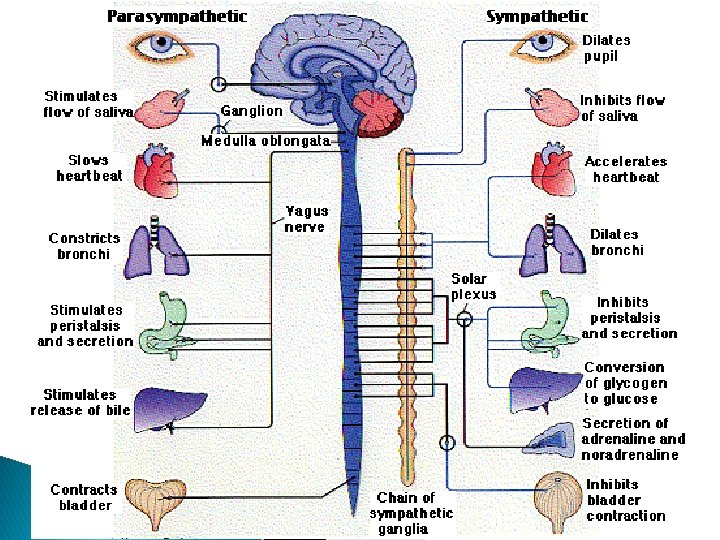

ÚTK: Autónóma taugakerfið � Ósjálfráða taugakerfið (autonomic nervous system) � Taugahnoð (ganglia) autónóma taugakerfisins liggja utan við mænu. Preganglion þræðir liggja frá heila og mænu í hnoðin. Postganglion þræðir liggja frá hnoðunum til marklíffæra

ÚTK: Autónóma taugakerfið � Sympatíska (sympathetic) taugakerfið: ◦ Sympatískir preganglíon þræðir ganga einvörðungu út á bróst- og lendarsvæðum ◦ Þeir eru stuttir og tengjast keðju hnoða rétt utan við mænu (sympathetic chain). Þaðan ganga langir postganglion þræðir til marklíffæra ◦ Í einfaldaðri mynd er hlutverk sympatíska taugakerfisins að sjá um svokallað “hrökkva-eðastökkva” viðbragð (fight-or-flight)

ÚTK: Autónóma taugakerfið � Parasympatíska taugakerfið: (parasympathetic) ◦ Parasympatísk hnoð liggja nálægt marklíffærum og þess vegna eru preganglíon þræðirnir langir ◦ Preganglíon þræðirnir ganga út úr spjaldhryggsvæði mænu og einnig eru heilataugar sem bera parasympatísk boð